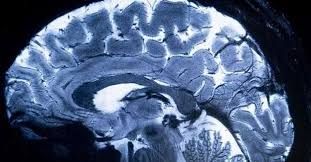

A OMS pediu nesta terça-feira (14), em caráter de urgência, mais atenção às doenças neurológicas, muitas delas preveníveis ou tratáveis, que afetam mais de três bilhões de pessoas.

As doenças neurológicas afetam mais de 40% da população mundial e provocam mais de 11 milhões de mortes a cada ano, segundo a OMS.

As dez condições neurológicas que mais contribuem para a morte e a incapacidade são o AVC, a enxaqueca, a doença de Alzheimer e outras demências, a meningite e a epilepsia idiopática, segundo os dados mais recentes disponíveis, de 2021.